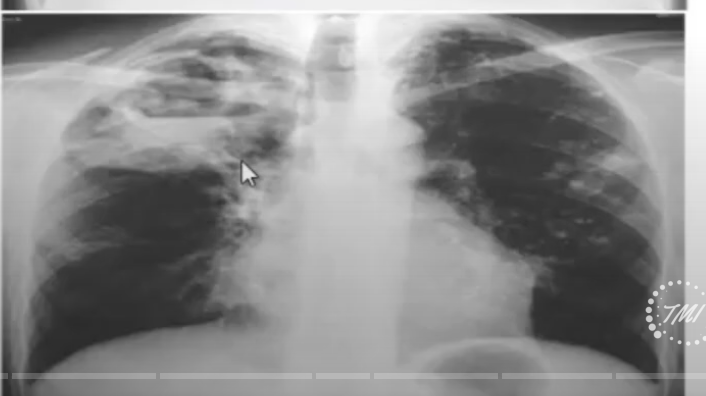

Manifestacion por imagen de una infeccion primaria progresiva

Manifestacion por imagen de una TB secundaria es decir reactivacion